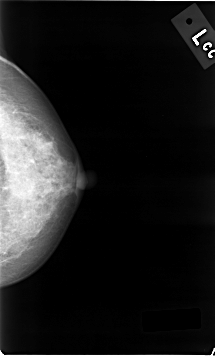

C_0015_1.LEFT_CC

LEFT_CC LINES 4648 PIXELS_PER_LINE 2784 BITS_PER_PIXEL 12 RESOLUTION 50 NON_OVERLAY